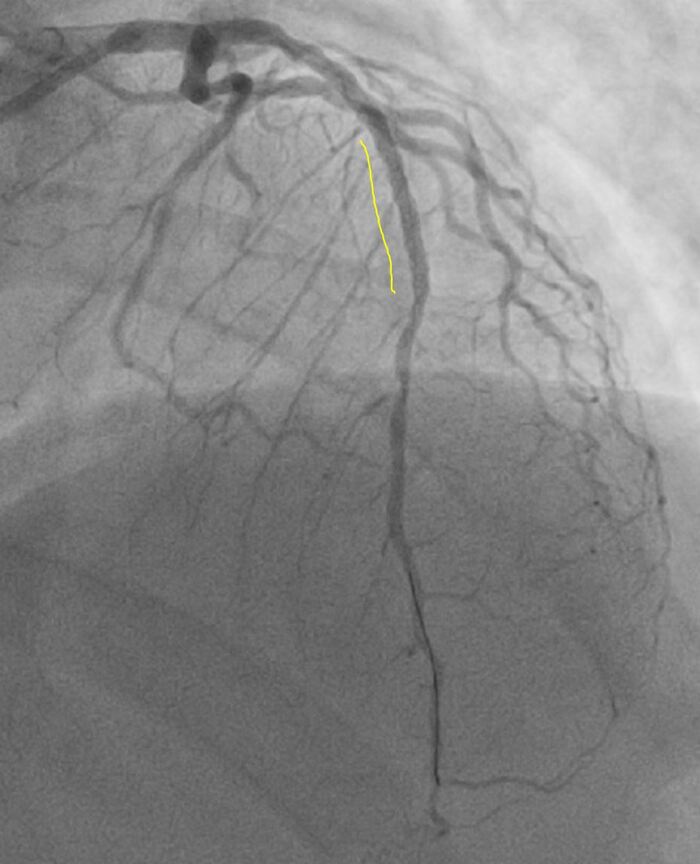

Оператор, с учетом такой картины, решает уточнить морфологию поражения, для выбора правильной тактики лечения (то что это нужно стентировать сомнений нет).

Делает ВСУЗИ (внутрисосудистое ультразвуковое исследование = специальный датчик заводится в сосуд через катетер и он изнутри датчик сканирует сосуд ультразвуком, в нашем случае частотой 40 Мгц)

Картина на ВСУЗИ:

Выявлена в начальном сегменте ПМЖА большая нестабильная атерома (желтым) с липидным ядром с распадом, на устье ПМЖА уже сформирована фиброзная атеросклеротическая бляшка (красным) с переходом на ствол левой коронарной артерии. Сама артерия по ВСУЗИ большая